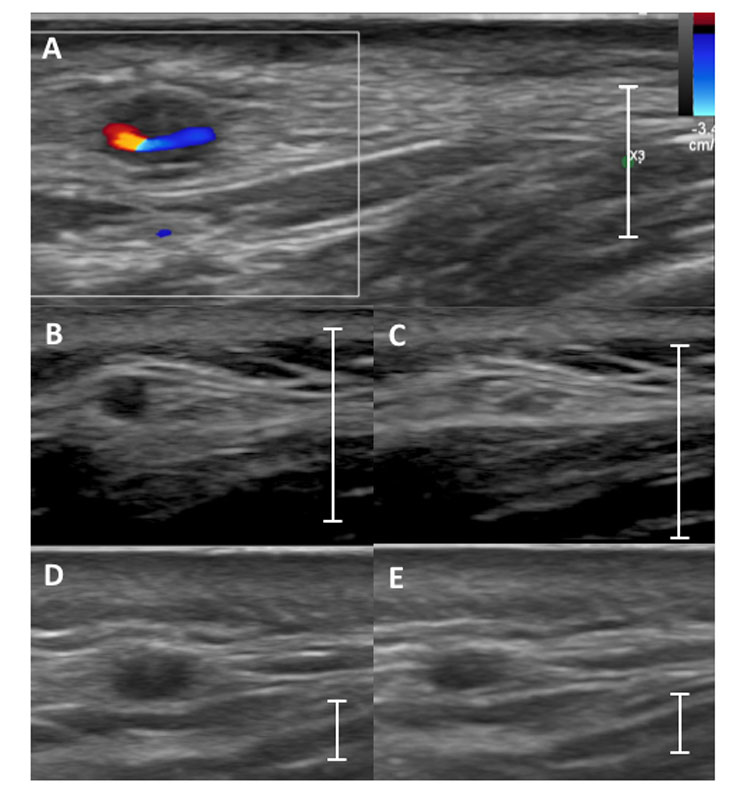

Colour duplex sonography (CDS) assesses the vascular wall anatomy as well as the lumen and it allows the measurement of blood flow. Vasculitis of the temporal arteries shows as homogenous, typically hypoechogenic (dark), circumferential vessel wall thickening. At the temporal arteries, this finding is referred to as the “halo sign”, because of the halo-like appearance around the coloured lumen in cross-sections (fig. 1A) [17]. We recently established the “compression sign”: when applying transducer-imposed pressure on the temporal arteries, a non-vasculitic artery can be compressed and vanishes on the B-mode image (fig. 1B, C). In contrast, an artery with vasculitis-associated wall thickening is not fully compressible and remains visible under compression (fig. 1D, E). The compression sign relies on B-mode ultrasound only, making it less examiner- and device-dependent. Nonetheless, it still has a sensitivity and specificity comparable to the halo sign [18]. As with temporal arteries, vasculitis of large arteries (e.g., axillary, carotid) also presents as circumferential homogenous hypoechogenic wall thickening (fig. 2A). Stenosis, or even occlusion, can be present. In lower limb arteries an echo-lucent ribbon within the thickened wall can be another sign of vasculitis [7]. In contrast to vasculitis, advanced arteriosclerosis shows more heterogeneous, eccentric, irregular plaques, typically with acoustic shadowing mostly in the carotid and femoral and popliteal arteries (fig. 2B).

Figure 1 Typical aspect of vasculitis in temporal arteries. (A) Example of the halo sign: a hypoechoic vessel wall around the colour-filled remaining lumen in colour Doppler mode. (B) A noninflamed frontal temporal artery without compression that with (C) a complete lack of visibility of the artery wall upon compression in B-mode = negative compression sign. (D) A temporal artery with vasculitis with a positive compression sign: frontal temporal artery without compression (D) and remaining visibility of the artery upon compression (E) in B-mode is shown. The line indicates the scale of 1 cm.